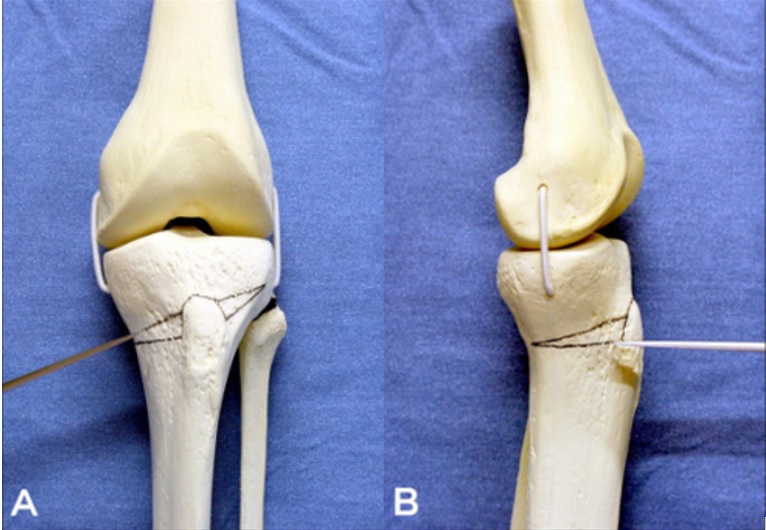

Un alignement des os pour arrêter le processus d’usure asymétrique